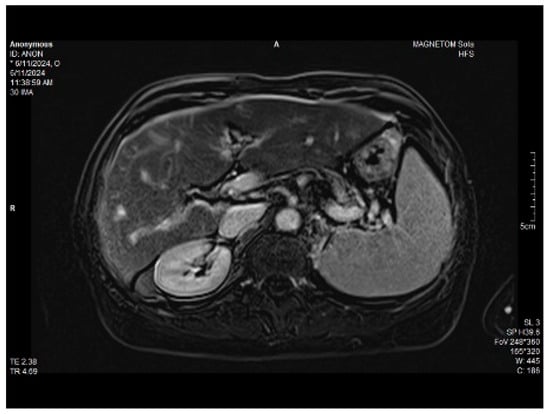

Abdominal MRI study confirmed the hepato-splenomegaly, ascites and the patency of the portal vein system. In addition, small veno-portal shunts were highlighted at the periphery of both hepatic lobes. Various MRI features are depicted in Figure 6, Figure 7, Figure 8 and Figure 9.

Figure 7. MRI: splenomegaly.